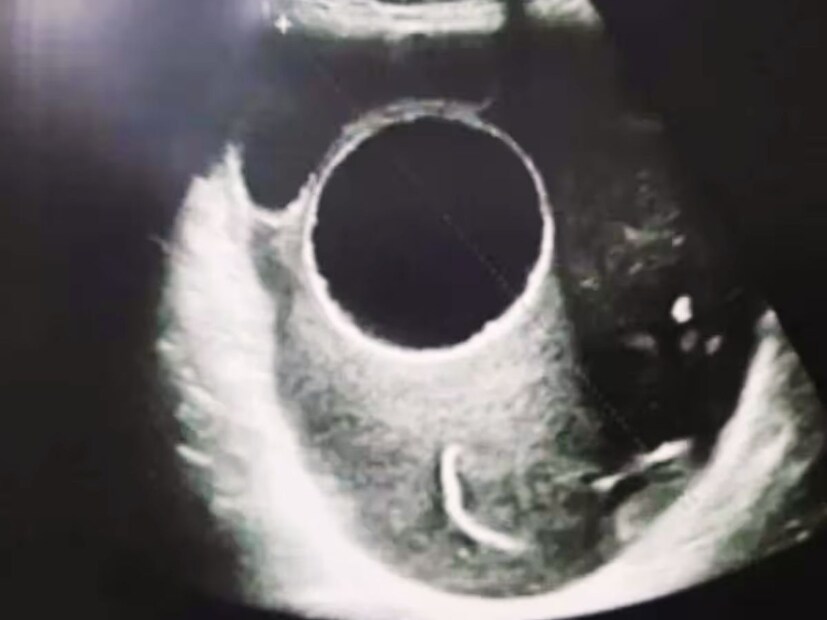

Tapeworm Attack in Brain: বর্ষার সময় একধরনের পরজীবী শরীরে ঢুকে মস্তিষ্কে সিস্ট তৈরি করতে পারে। চিকিৎসকরা বলছেন, যদি নিয়মিত মাথাব্যথা ও খিঁচুনির সমস্যা হয়, তাহলে অবহেলা না করে সঙ্গে সঙ্গে ডাক্তার দেখান। এটি প্রাণঘাতী রোগেও রূপ নিতে পারে। এটিকে টেপওয়ার্মও বলা হচ্ছে৷ অবহেলায় ভয়ঙ্কর ক্ষতি হতে পারে শরীরের, বিস্তারিত জানুন...